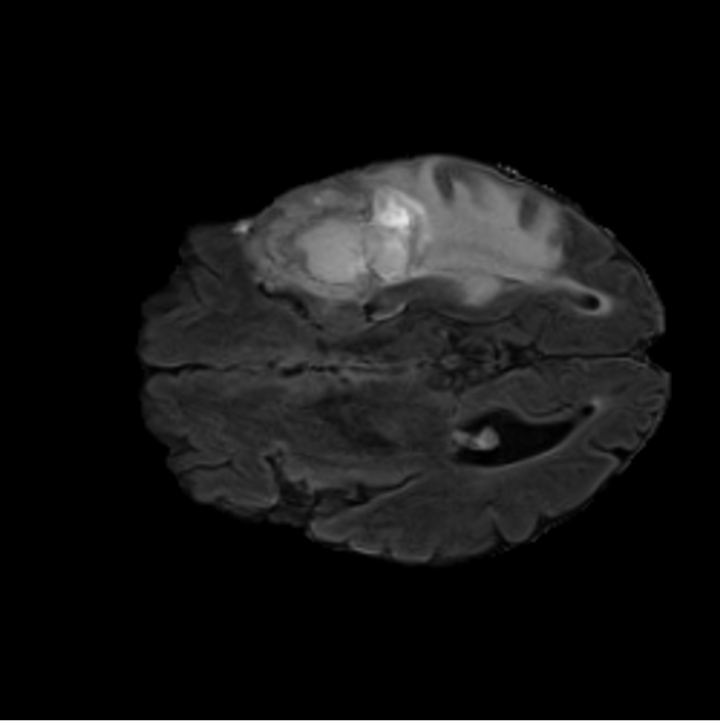

Tumour Information Preservation. For the brain tumor segmentation, we use a Swin UNETR model[27, 70], trained with random rotation, and intensity as data augmentation. In Figure 5, we highlight the tumor profiles of the generated MRIs compared to the ground truth tumour profile. In the test set with human ground-truth annotations (), the real MRI Dice score is 85.15 while the generated MRIs from a single slice have a dice score of 83.09. This shows how the generated MRIs indeed preserve the tumor information and can act as an affordable and informative pseudo-MRI, before conducting an actual costly MRI examination in hospitals.

BRATS. The largest public dataset of brain tumours consisting of 5,880 MRI scans from 1,470 brain diffuse glioma patients, and corresponding annotations of tumours[3, 42, 4]. All scans were skull-stripped and resampled to 1 mm isotropic resolution. All images have resolution 240 240 155, and we use the flair T2 sequence. Tumours are annotated by expert clinicians for three classes: Whole Tumour (WT), Tumour Core (TC), and Enhanced Tumour Core (ET). We split the 5,880 MRIs split into Train (n=4704), Validation (n=588), and Test (n=588) sets.

B.4 Tumour Information Preservation

On the test set with human ground-truth annotations (), the brain volumes generated from single slice input preserve the volume of the different tumour components (paired t-test, for all 3 classes) (see Table 3). The real MRI Dice scores are put for reference to our generated MRIs. X-Diffusion outperforms baselines TPDM [36] and ScoreMRI [18] in tumour preservation (see Table 3 and Figure 12). We ran experiments comparing the tumour segmentation Dice Score varying X-Diffusion configurations. The multi-slice input X-Diffusion achieves a marginally better Dice Score than the single-slice input model (83.47 83.09). We also ran experiments with slice input used for volume reconstruction intersecting or not with tumour. We observe on average a drop of 6% Dice Score (see Table 3). Further away from the tumour the input slice for volume reconstruction is selected, and we observe a linear decrease in tumour segmentation Dice Score with the lowest value of 77.21 Dice Score (see Figure 15).